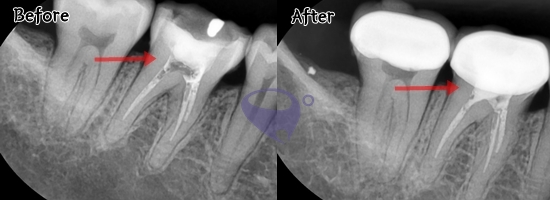

#患者二 #根管治疗 #再手术